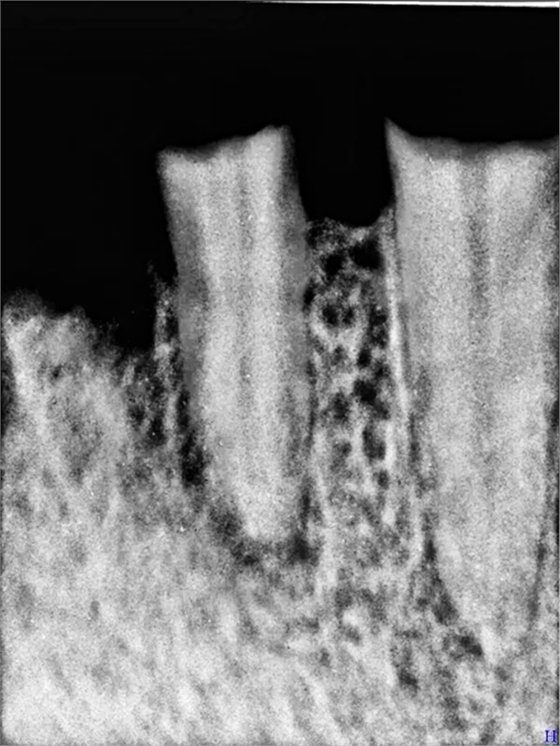

口腔檢查:22深齲有瘺管 23 24殘根,15近遠(yuǎn)中間隙(機(jī)械性片切造成),x片22 23 24 根尖低密度陰影

23 24 殘根是為“專家”做的固定義齒2帶3的固定橋造成的后果,“磚家”厲害啊

以上是口腔x片情況,由于患者把原義齒丟棄,沒(méi)有照片但看15號(hào)牙情況,義齒應(yīng)該體積不小